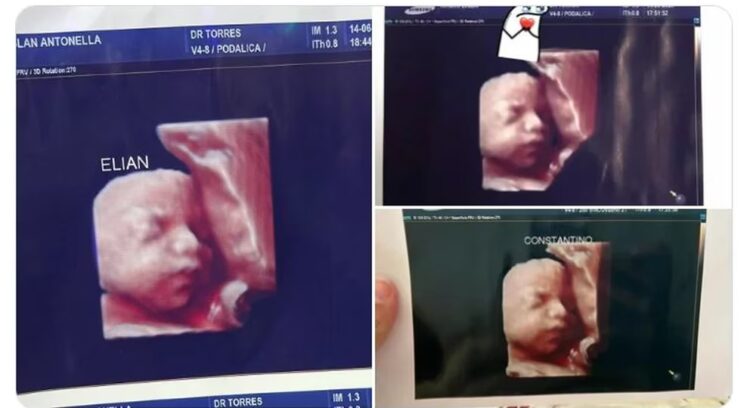

Un escándalo en la provincia de Formosa sacudió las redes sociales, luego de que varias mujeres denunciaron a través de plataformas como TikTok y Twitter que una clínica privada local utiliza la misma foto de una ecografía 5D para todas sus pacientes.

A los pocos minutos, otra mujer reconoció la imagen como la misma que le habían entregado a ella. Y luego, más mujeres se unieron a la conversación y se dieron cuenta de que todas tenían la misma foto de la ecografía, creyendo erróneamente que era la de sus propios hijos.

“Por ahora somos tres mamás a las que una clínica ESTAFÓ con una foto de un bebé que no es el nuestro”, denunció una de las mujeres en su cuenta de Twitter, adjuntando las ecografías falsas. Las imágenes supuestamente correspondían a bebés de sexo masculino, pero también se descubrió que se habían entregado a embarazadas que esperaban niñas.